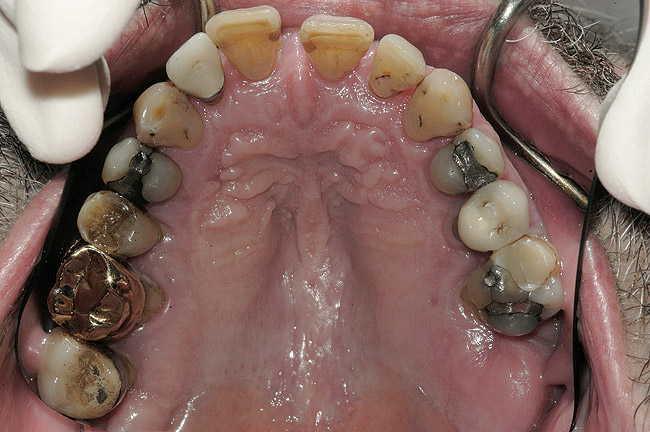

La examinarea clinică, o serie de dinţi prezentau restaurări directe mici acceptabile. Dinţii de la 1.7. la 1.4., de la 1.2. la 2.6., 3.6. şi 4.5. prezentau fie restaurări directe voluminoase, fie coroane cu acoperire totală, cu un grad ridicat de compromitere structurală. Nu s-au identificat leziuni carioase active. Implicarea pulpară era vizibilă la nivelul molarului 3.6.

Obiective terapeutice

Consideraţiile privind managementul riscului şi planul de tratament au fost elaborate utilizându-se o abordare sistematică. Tratamentul ar fi redus riscul biomecanic prin eliminarea dinţilor compromişi structural (fig. 3,4), cu diminuarea concomitentă a riscului funcţional prin crearea unei ocluzii în armonie cu articulaţiile. În plus, tratamentul ar fi redus riscul parodontal prin îndepărtarea dinţilor irecuperabili, cu implicare parodontală, (fig. 5) şi ar fi îmbunătăţit estetica prin ridicarea cu 3mm a planului ocluzal pentru a minimiza expunerea gingivală şi a rădăcinilor.5-8

În cursul consultaţiei cu parodontologul, s-a stabilit imposibilitatea menţinerii vreunui dinte. S-au identificat posibilele lăcaşuri pentru implantare prin utilizarea radiografiilor şi a modelelor de studiu.